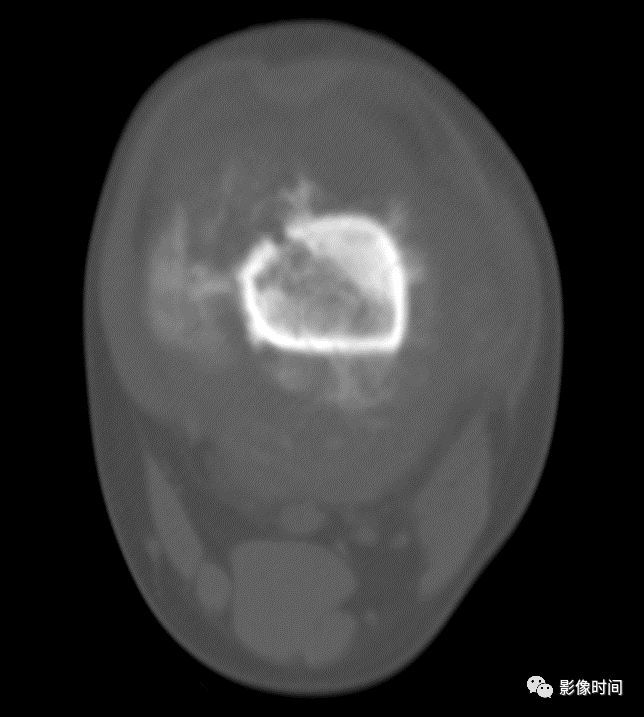

四、肿瘤内液-液平面

肿瘤内液-液平面多数是病灶内囊变出血所致,MRI T2W1 为上部呈高信号下部呈中低信号的液-液平面。CT 可为上部低密度下部高密度的液-液平面(图 32)。液-液平面常见于动脉瘤样骨囊肿、但也可见于骨内腱鞘囊肿(图 33)、囊性血管瘤病等其他肿瘤和肿瘤样病变。

图 32 肿瘤内液-液平面:动脉瘤样骨囊肿

图 33  肿瘤内液-液平面:动脉瘤样骨囊肿